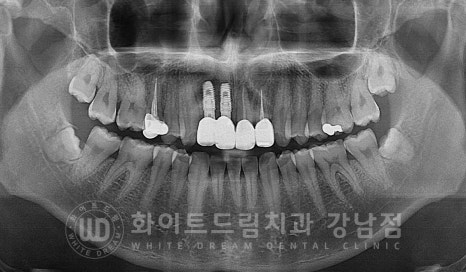

환자분은 수술 당일 골이식 + 임플란트 식립을 함께 진행하면서

2차 수술까지 한 번에 진행을 했습니다.

수술 당시 사진입니다.

▲ 앞니 임플란트 수술일자 : 23.05.04

2차 수술 시 체결하는 힐링 어버트먼트까지 체결된 것이 확인됩니다.

2차 수술까지 한 번에 진행할 때는 이렇게 잇몸의 높이와 힐링 어버트먼트가 같은 높이에 있어야

잇몸이 예쁘게 잘 아물게 된답니다.

또한 치아 사이, 간격이 좁은 부위에 임플란트를 식립할 때는

인접치와 어느 정도 거리를 두고 식립해야 하는데요.

인접치의 치근과 최소 1.5mm의 거리를 확보한 후 식립해야

인접치의 손상과 합병증을 예방할 수 있는데요.

인접치와 임플란트가 과도하게 가까우면

임플란트가 감염되거나 골흡수 등의 이유로 실패하거나

단기간 내 임플란트가 흔들리거나 주위 염증이 발생해 제거하게 되는 문제가 발생할 수 있습니다.

인접치는

치주 인대와 주변조직의 상실이 일어나 치아의 생활력을 상실하거나 치근단염, 치근흡수 등이

발생할 수 있답니다.

▲ 환자분의 식립 후 치근단 사진

인접치와 임플란트 사이 일정 공간을 확보하여 잘 식립된 것이 확인됩니다.